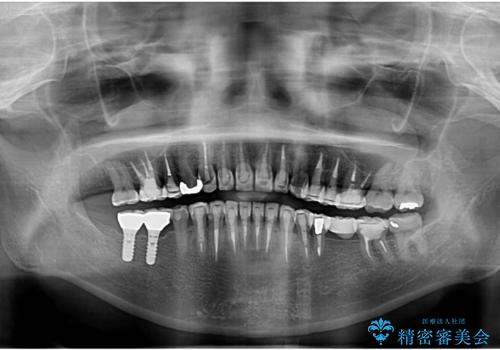

- 下顎の前歯に激痛を覚えて来院された患者様です。

取り急ぎ下顎前歯数歯の根管治療を、銀座しらゆり歯科医院長の林先生にお願いし、それ以外に気になっている、不自然な色調のクラウン、金属部分が見えてブラッシングがしにくいインプラント補綴、口元の突出感、出血のしやすい歯周ポケットなど、全てを解決するための治療を行うこととしました。